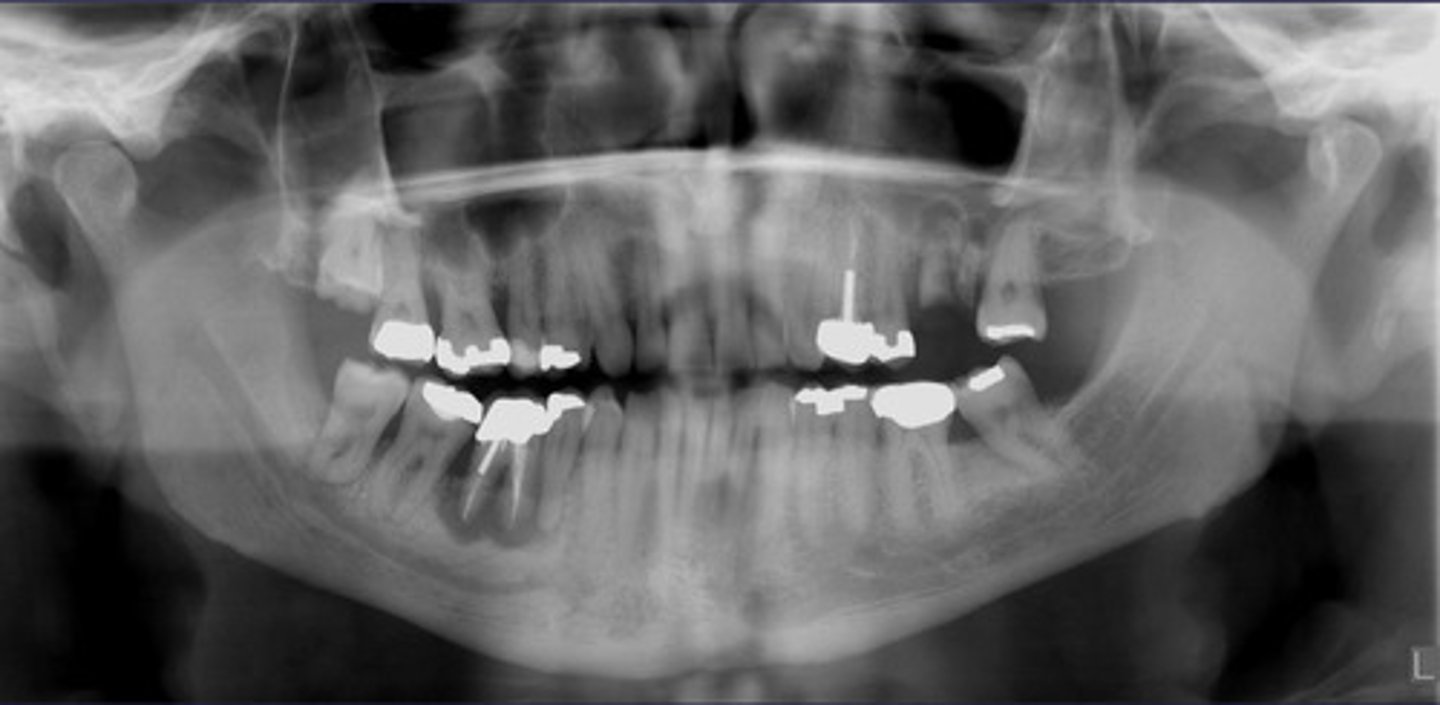

How would you describe the lesion?

- Ill-defined, moth eaten area in the posterior mandible

- How would you describe the lesion?

What category would you put this lesion into?

malignant

all of the following could be a differential diagnosis for this lesion except?

A. squamous cell carcinoma

B. multiple myeloma

C. osteogenic sarcoma

- Ill-defined moth eaten area in the posterior mandible

- Radiopacities extending beyond the mandibular borders.

What would be a differential diagnosis for this lesion?

- Osteogenic sarcoma

- Squamous cell CA